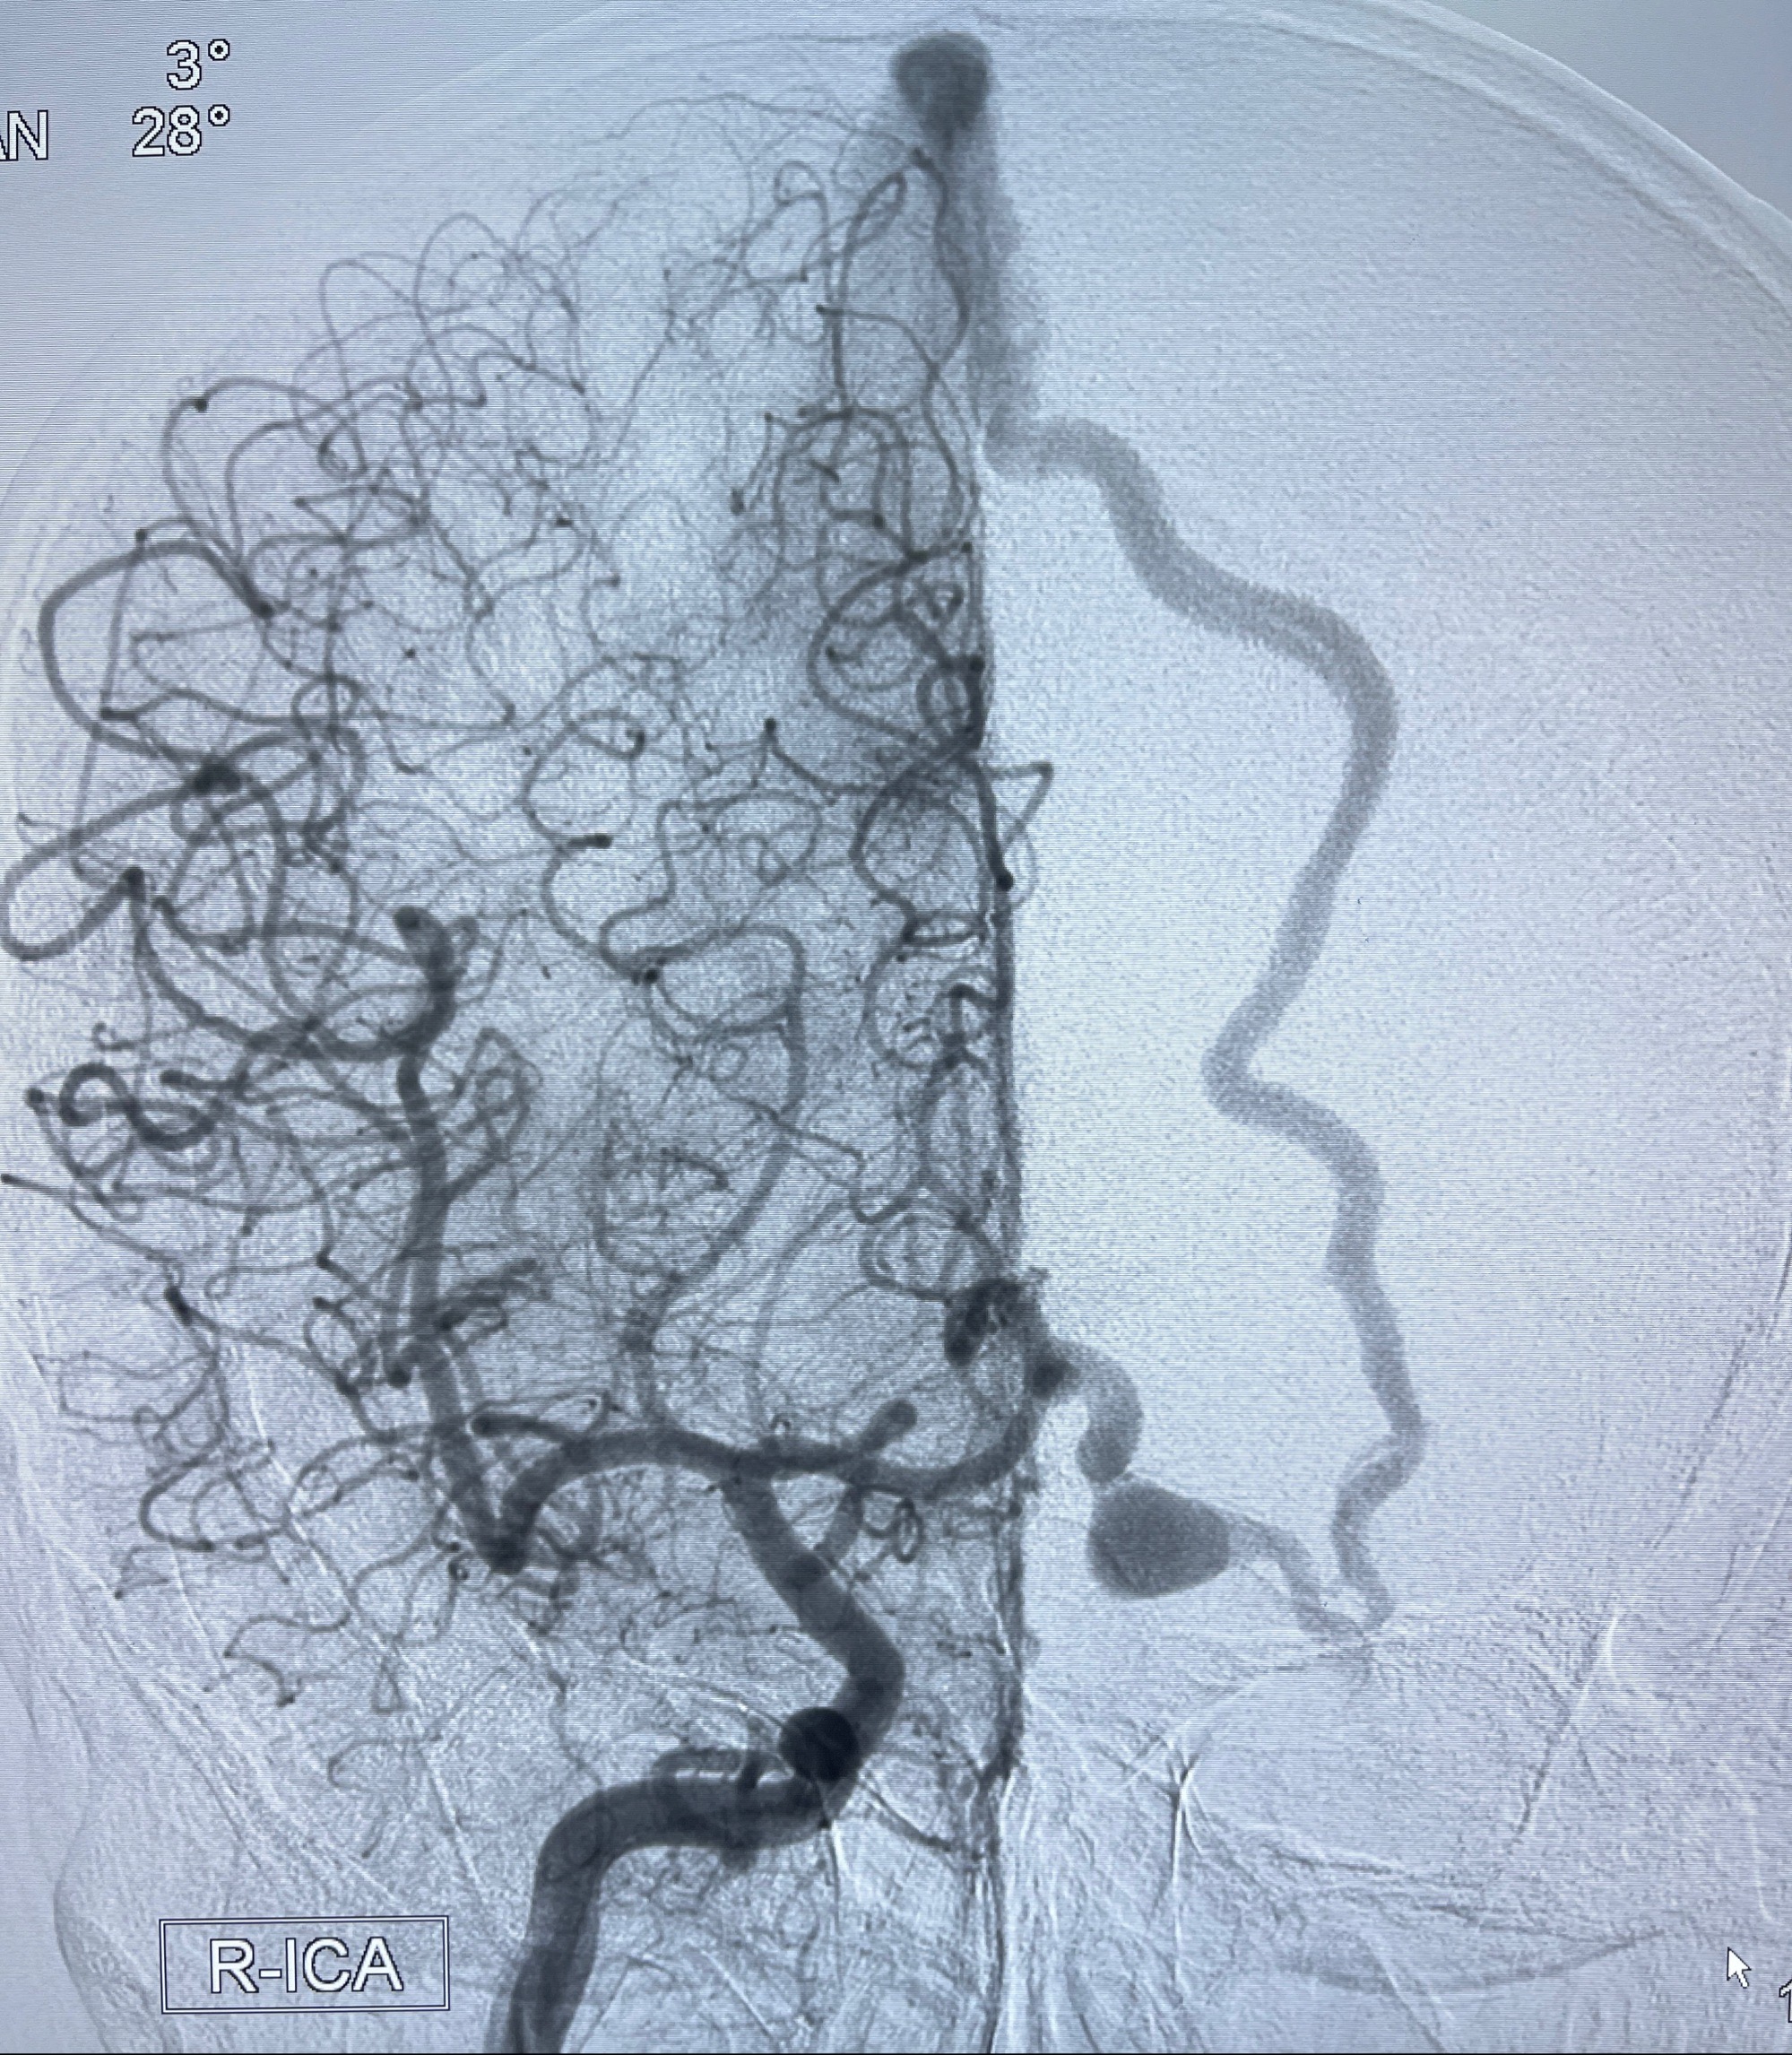

2023年8月21日]景德镇市第一人民医院脑血管造影检查,提示:主动脉弓、双侧颈总动脉、锁骨下动脉造影未见异常,左侧大脑前动脉静脉瘘。

2023-09-13全脑血管造影:前颅底硬脑膜动静脉瘘,供血动脉为双侧胼周动脉、眼动脉脑膜支,静脉向上矢状窦方向引流